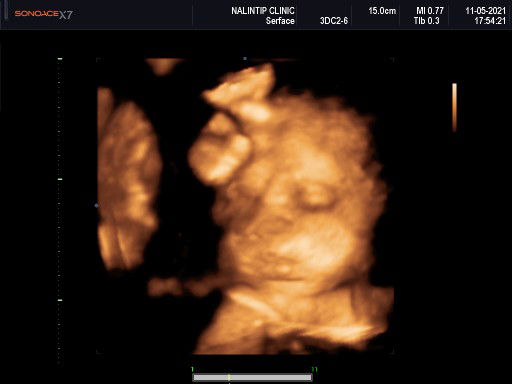

นี่เลยจ้าา 37วีคแล้ว

กลมๆแบบนี้ครับบ🥳🥳

อลิน ตอนนี้35วีคค่ะ

ลูกสาวค่ะ ซาวตอน27w